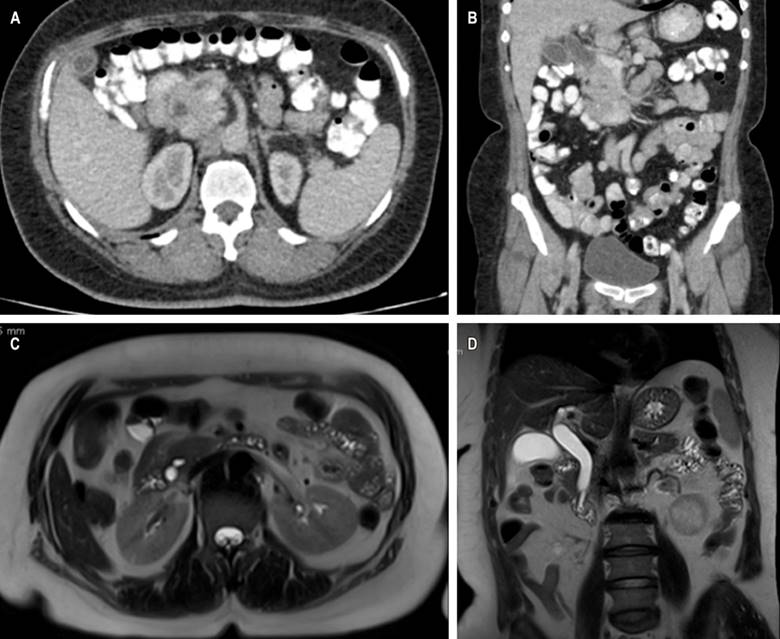

This is a 58-year-old woman with a history of hypertension and diabetes mellitus who does not require insulin and who consulted after 20 days of abdominal pain in the left hypochondrium, stabbing type, that expanded to the epigastrium with an intensity 6/10 on the analogous scale of pain associated with generalized jaundiced dye, acolia, choluria, and febrile peaks quantified up to 39 ºC. She underwent some laboratory studies that evidenced hyperbilirubinemia at the expense of direct bilirubin and elevated transaminases. The ultrasound showed hepatic steatosis, the gallbladder without stones inside associated with dilated intra- and extrahepatic bile duct with a common bile duct of 12 mm but did not show the cause of the obstruction. She also underwent a computed tomography (CT) scan and magnetic resonance cholangiopancreatography (Figure 1), which showed dilation of the bile duct secondary to distal choledocholithiasis, and it was decided to take her to endoscopic retrograde cholangiopancreatography (ERCP) to perform the management of obstructive biliary syndrome that had a probable biliary origin. However, a large papilla of neoplastic appearance of 3 centimeters at its greatest diameter was found without canalizing the bile duct. The patient underwent a biopsy and magnetic resonance imaging with double contrast (Figure 2) that reported choledocholithiasis, dilatation of the intra- and extrahepatic bile duct, and dilation of the intrapancreatic duct due to probable periampullary neoplasia.

Figure 1 CT scan with evidence of intra- and extrahepatic bile duct dilation (A) axial section (B), and coronal section. Cholangioresonance shows dilation of the bile duct secondary to choledocholithiasis (C) in the axial section and (D) coronal section. Source: Authors’ archive.